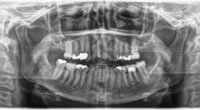

従来のレントゲン画像は2D(平面)であったため、画像が重なっている場合や骨の厚みがとてもある場合など、レントゲンが撮影できない金属がある場合など、正確な顎骨の中の状態を把握することが困難でした。

しかし、CTレントゲンは3D(立体的)での画像が得られ、従来の平面レントゲン画像に比べ、より豊富な情報を歯科医師に提供するレントゲンシステムです。

インプラント治療計画、歯周外科治療での使用にとどまらず、今後の歯科診療において、治療の安全性と確実性を向上させるために不可欠なものとされています。